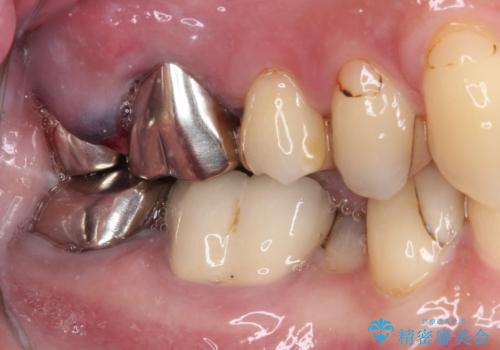

- 目立つ銀歯と欠けて痛みを感じる歯を気にして来院された患者様です。

手前の歯は神経の炎症がとても強く、保存不可能であったため、根管治療を行うこととしました。

目立つ銀歯も根管治療を行い、その後2本の歯をオールセラミッククラウンにて補綴治療を行うこととしました。